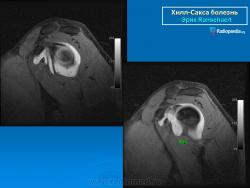

На рентгенограмме плечевого сустава определяется умеренный остеопороз головки плечевой кости. Иногда на ее задненаружной поверхности позади вершины большого бугорка выявляется вдавленный дефект (повреждение Хилл-Сакса). Дефект четко виден на рентгенограмме в аксиальной проекции. Аналогичный, но менее выраженный дефект может быть выявлен в зоне передненаружного края суставной впадины лопатки. Также в диагностике причин привычного вывиха плеча помогает МРТ исследование.